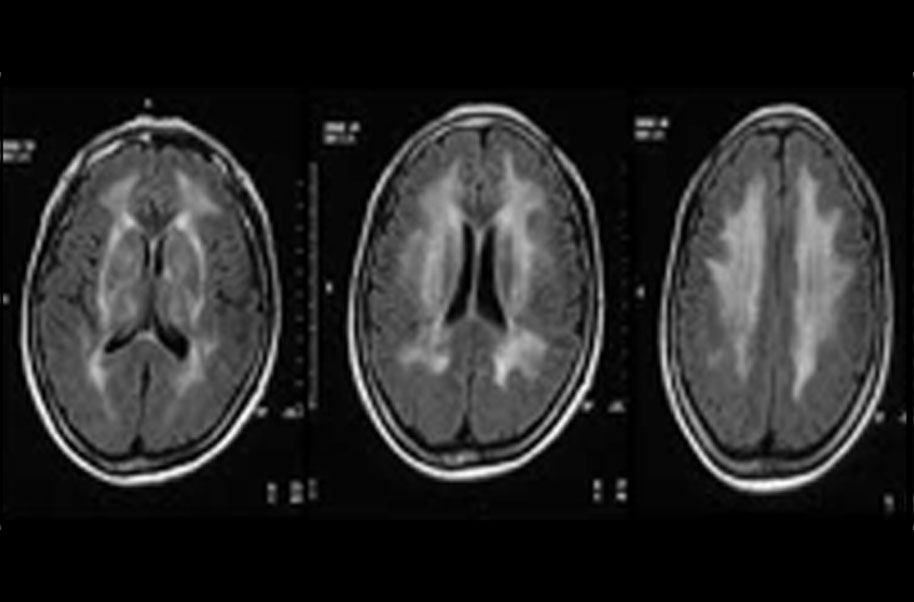

Subcortical Leukoencephalopathy

Binswanger's disease, also known as subcortical leukoencephalopathy, is a form of small vessel vascular dementia caused by damage to the white brain matter. White matter atrophy can be caused by many circumstances including chronic hypertension as well as old age.